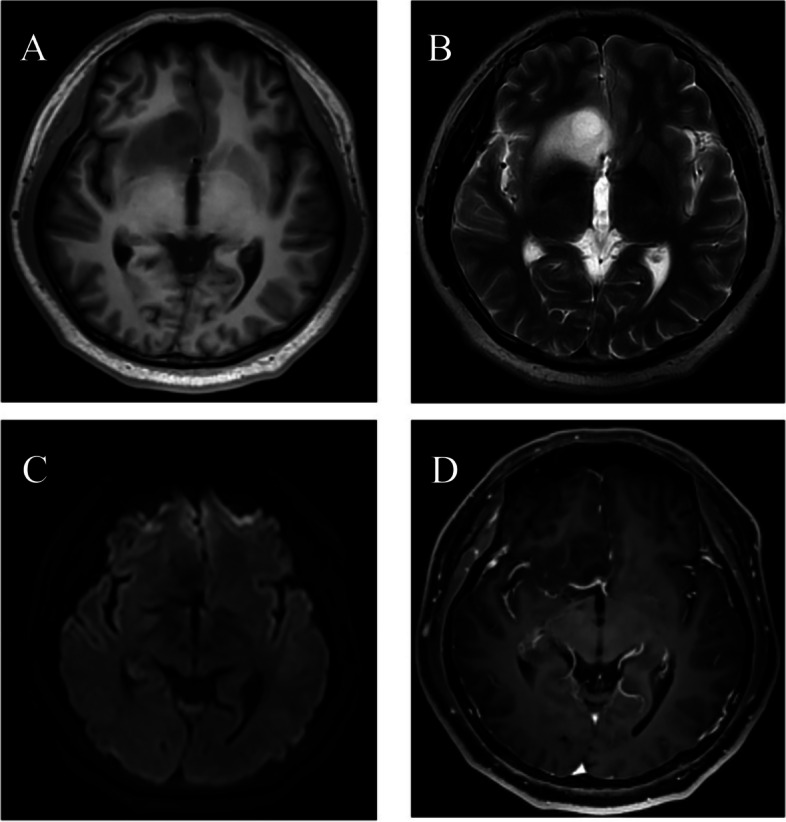

Results: Twenty patients, including 7 males (55%) and 13 females (45%), with a mean age at diagnosis of 37.9 years (range, 28-53 years) underwent operative intervention for APS. Headaches and dizziness were the most common preoperative symptoms in the majority patients (14, 70%). Based on radiological features of MRI, the APS was classified into two subtypes, type A and type B. Seven patients (40%) in type A indicated a clear tumor margin, while 13 patients (60%) in type B showed an ill-defined margin. The surgical approach including frontal, temporal, and coronal frontal incisions for type A and type B tumors, respectively. Three patients in type A received total resection, while one patient in type B were total resected. Pathologically, 12 cases (60%, 12/20) were diagnosed as astrocytoma and 8 cases (20%, 8/20) were oligodendroglioma. Meanwhile, 17 cases (85%, 17/20) had MGMT promotor methylation.

Conclusion: In this study, we performed the first systematic research of patients with APS glioma. Most of patients with APS presented headaches and dizziness symptoms. The APS glioma was further divided into two major radiological subtypes with relevant different surgical approaches. The APS glioma in type A were more likely to receive total resection.